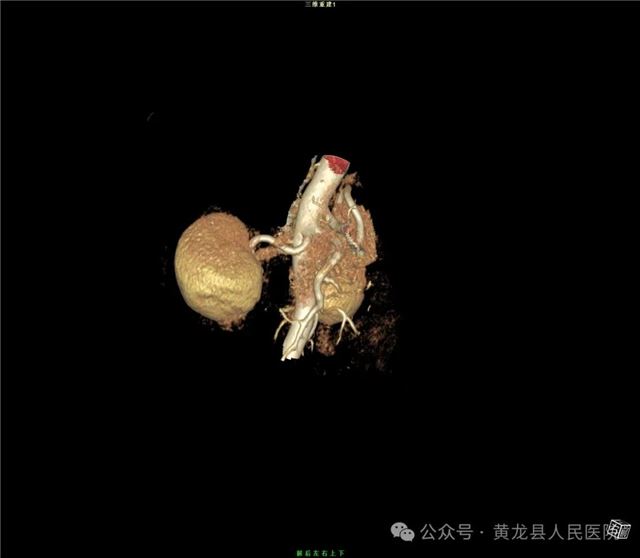

双肾增强CT

双肾VR